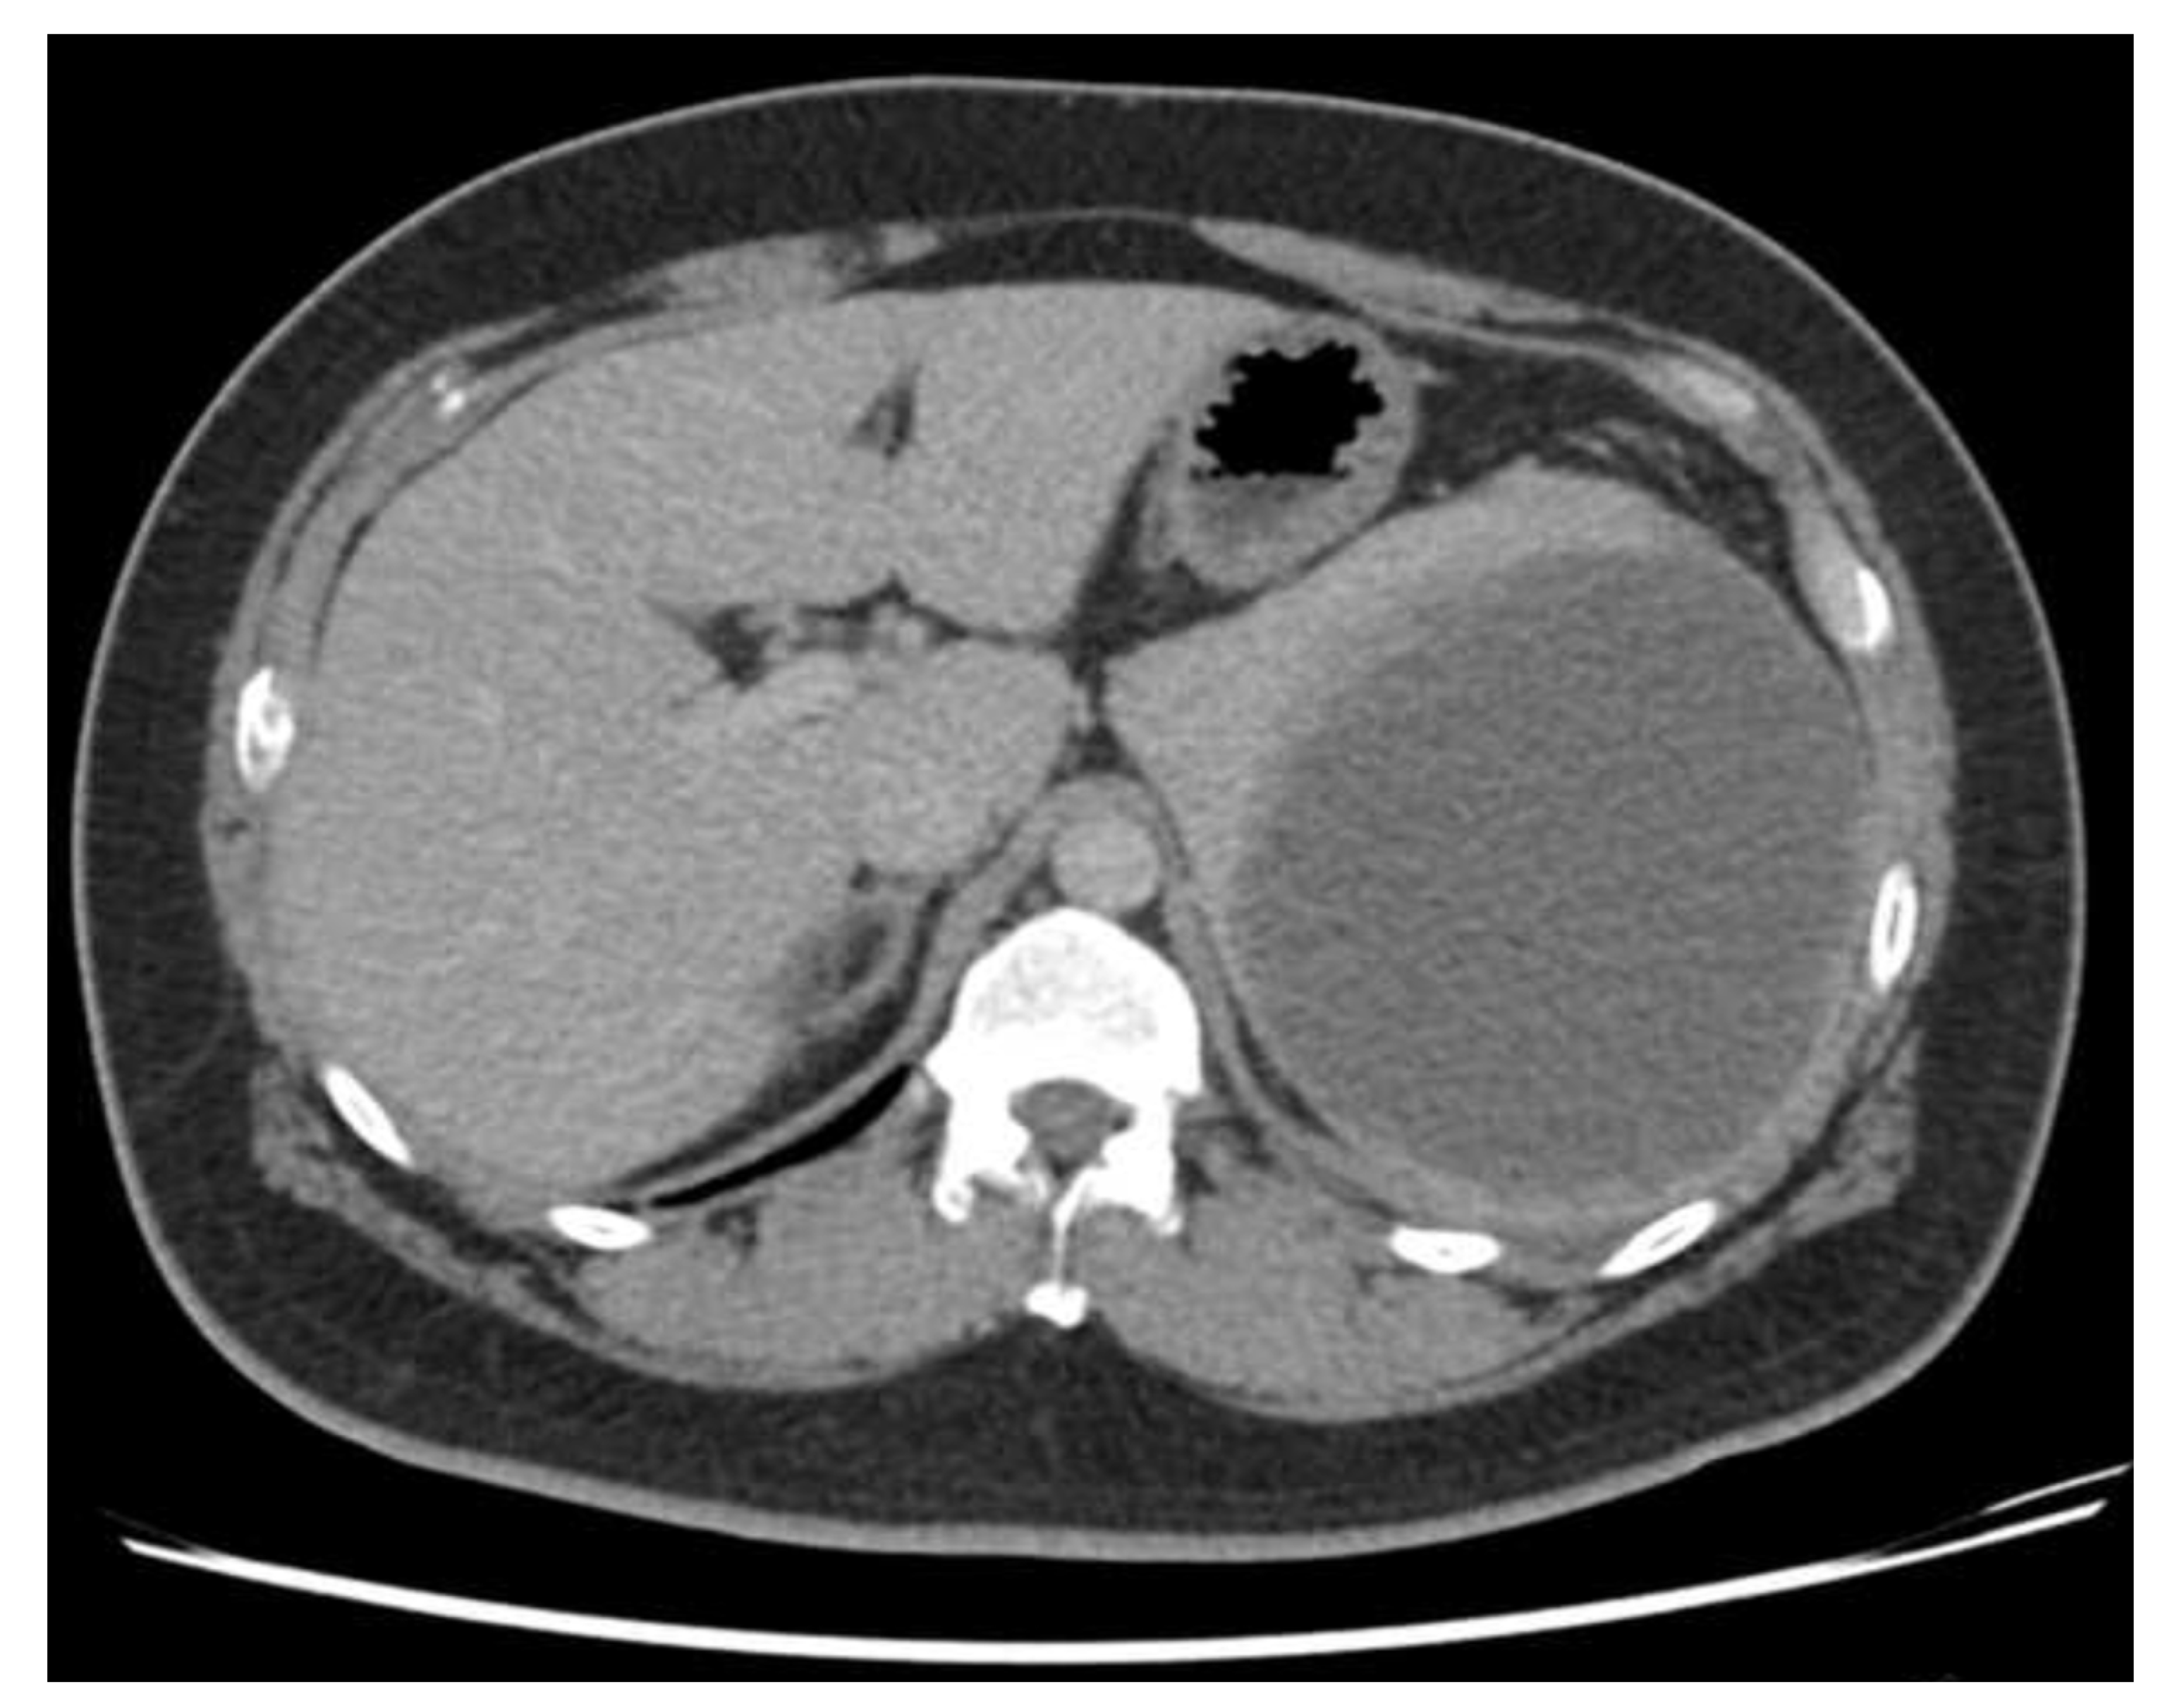

Physical examination revealed a large palpable mass with local tenderness over the LUQ. The patient’s white blood cell count was 17,000/μL, with segment neutrophil 83% and lymphocyte 10%, and platelet: 475,000/mL. An abdominal computed tomographic (CT) scan revealed a large cystic splenic mass measuring 14 cm without enhancement after contrast medium (Figure 2). The mass was pushing the left kidney inward and down (Figure 3). During the initial diagnosis, a pancreatic pseudocyst involving the spleen was suspected, and the patient received an emergency splenectomy because of the rapid growth of the mass and severe pain.

Figure 2.

Abdominal CT scan revealed a large cystic splenic mass measuring 14 cm without enhancement.